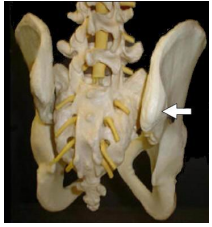

23 下圖為腰骶骨盆區的骨頭模型,箭頭所標示的結構為何?

(A)髂後上棘(posterior superior iliac spine) (B)髂前上棘(anterior superior iliac spine) (C)髂棘(iliac crest) (D)坐骨棘(ischial spine)